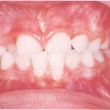

Mordida cruzada: Tratamento precoce é a solução

Deslizamento dos dentes na mordida, inflamação gengival, danos à estrutura dental. Tudo isso pode ser evitado com um tratamento adequado, feito no momento certo. São problemas que podem surgir devido(...)